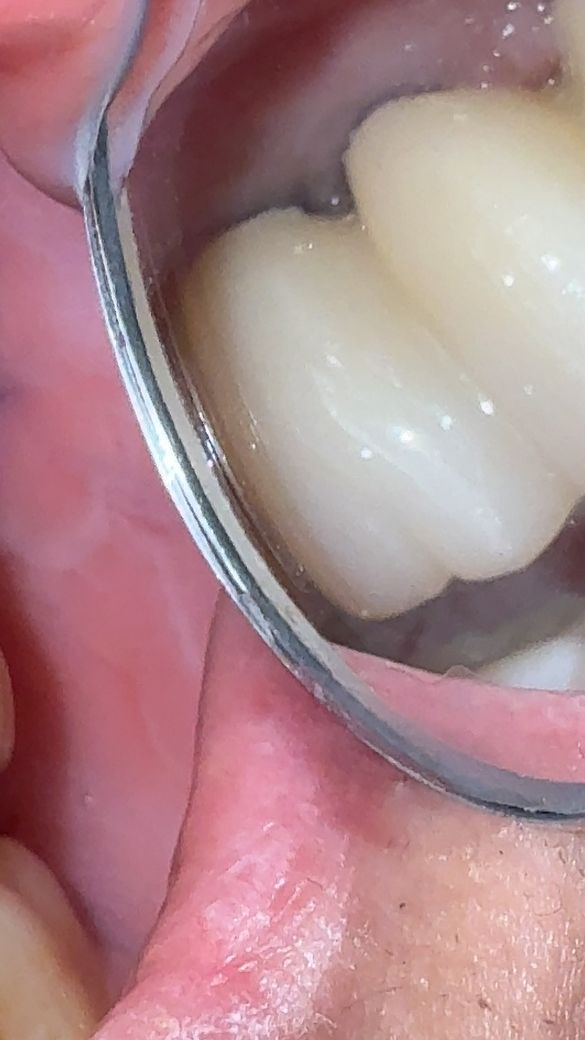

사진은 윗쪽 브릿지형 보철물 사이 협측의 모습인데

얼마전 프라그가 좀 끼인거같아 회사근처 치과로 내원 후 소독&제거를 받았는데 보시다시피 보철물사이에 검은공간이 보여서 혹시 주위염이 발생한건지 고견을 듣고싶습니다(구멍이 크진 않으나 저런 검은 공간이나 경계면?이라고 해야할지 잇몸과 보철물 사이의 검은부분도 신경이 쓰이네요..)

• 1번 째 사진

사진에 보이는는 정도는 괜찮습니다. 잇몸부위에 맞춰서 제작을 하지만 잇몸이 조금씩 내려가면서 약간 틈이 생긴거 같습니다.